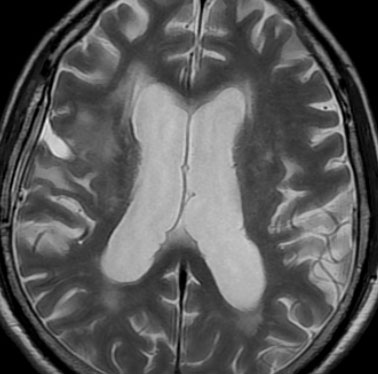

2年後 放射線壊死の進行

定位放射線治療後約2年,前の画像からはわずか3ヶ月後のMRIです。また右前頭葉の転移病巣が再発したかのように見えます。周囲の浮腫も広がって,左の片麻痺が悪化しました。しかし,ガドリニウム増強されて白くリング状に写る部分が不整形でまわりがギザギザしています。ステロイドを投与しましたが改善せずに悪化傾向を示しました。

手術後の脳浮腫の改善

手術で放射線壊死巣を摘出してから1月半後のMRIです。放射線壊死が摘出されて,脳浮腫もかなり改善しました。同時に右麻痺もよくなってきました。

この例では,アバスチンを投与するという選択肢もあったのですが,医療費が高額で患者さんが経済的に耐えられません。